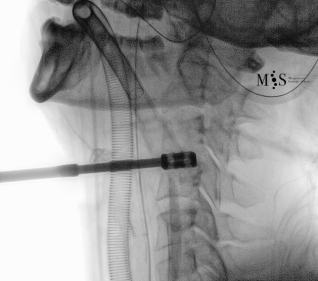

Images showing the endoscopic placement of a cage into a cervical disk

Animated image showing the endoscopic insertion of an intervertebral cage into a cervical disk.

Note the distraction of the disk space during as the cage is inserted.